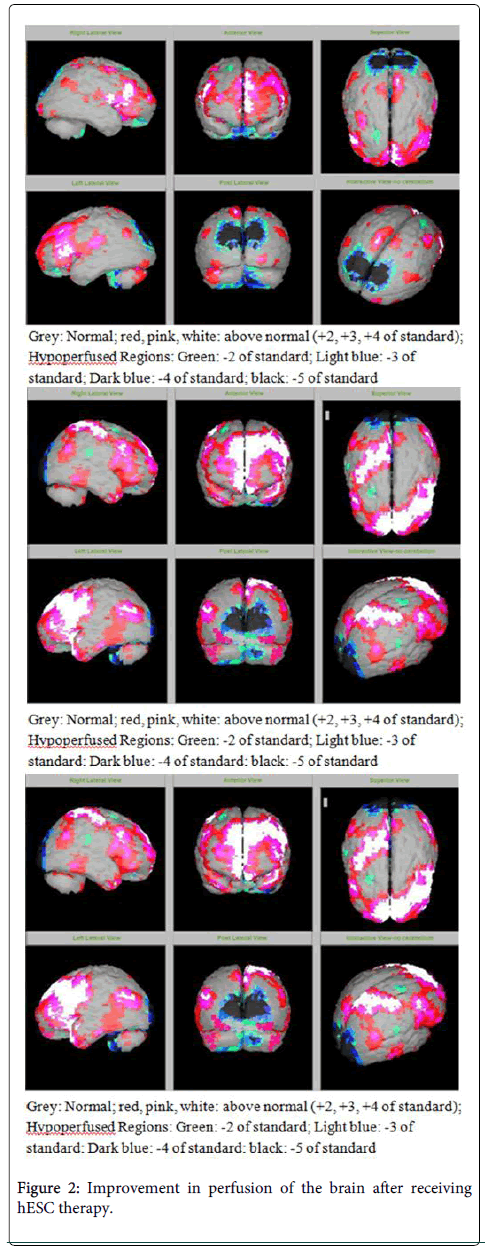

圖2:接受hESC治療后大腦灌注得到改善

SPECT掃描

在研究開始和結(jié)束時(shí),23名患者接受了SPECT掃描。在枕葉或額葉或雙葉中觀察到灌注不足。23例接受SPECT掃描的患者中,5例患者表現(xiàn)為枕葉灌注不足,7例患者表現(xiàn)為額葉灌注不足,11例患者表現(xiàn)為枕葉和額葉灌注不足。

總體而言,治療結(jié)束時(shí),2名患者的灌注正常,18名患者(12名男性和6名女性患者)顯示灌注顯著改善(>60%),3名患者顯示灌注中度改善(30-60%)。大多數(shù)在接受hESC治療前額葉和枕葉嚴(yán)重低灌注的患者在接受 hESC 治療后情況有所改善。23名可獲得SPECT掃描報(bào)告的患者的GMFCS評(píng)分在hESC治療后有所改善(表2)。

眾所周知,神經(jīng)干細(xì)胞可以通過重新填充受損區(qū)域并防止細(xì)胞進(jìn)一步退化來恢復(fù)正常視力。hESC通過增殖成相似的細(xì)胞類型來啟動(dòng)受損細(xì)胞的再生。在本研究中觀察到灌注改善,這反映在SPECT掃描中。詹森等人研究顯示,一名5歲腦癱患者在接受臍帶血干細(xì)胞治療2個(gè)月后視力有所改善。